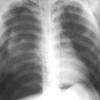

2 deep sulcus